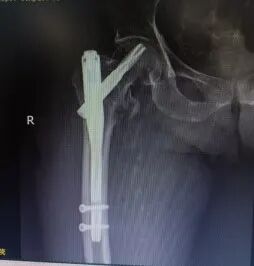

专家团队为其制定了周密的围手术期方案:积极纠正心功能不全,有效控制肺部感染,并精准调控血糖、纠正酮症酸中毒及电解质紊乱。在患者状态趋于稳定后,经麻醉科全面评估并实施精准麻醉,最终顺利完成了手术。

左图为X光 股骨粗隆间骨折;术后内固定术后